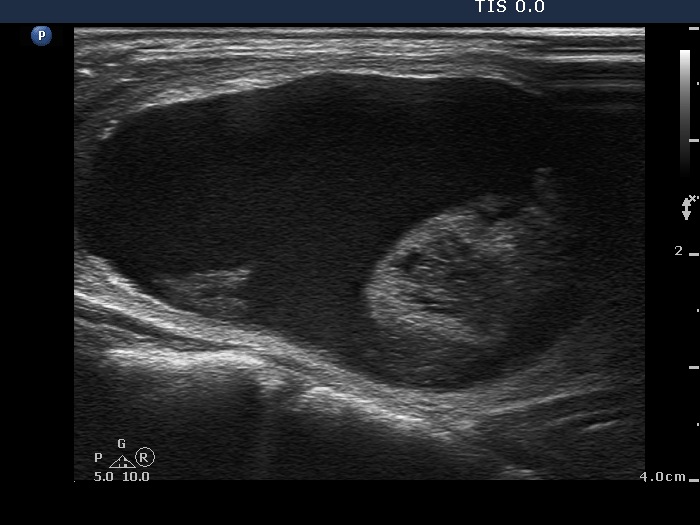

Ethanol sclerotherapy: other examples - Case 3: treatment of a gelatinous thyroid cyst

Second session of therapy (ultrasonographic picture 2)

Right lobe, longitudinal scan.